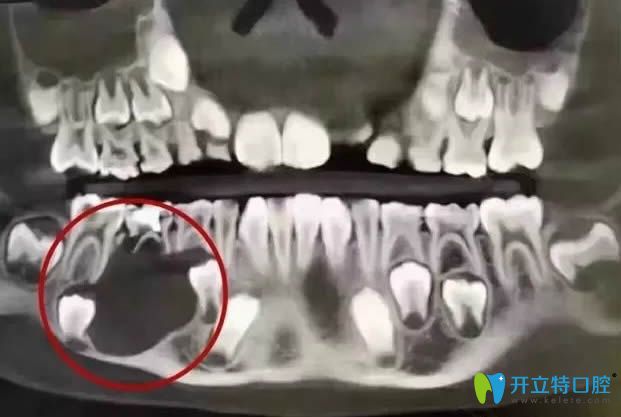

<這就是那位12歲小姑娘的口腔全景CT圖>

被切除下頜骨的口腔全景CT圖

看了這位小姑娘的病例以后,你還會(huì)疑惑乳牙壞了是否會(huì)影響恒牙嗎?你還會(huì)覺得乳牙齲壞不用補(bǔ),反正是要換新牙的嗎?